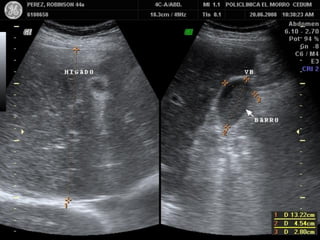

VESICULA CONTRAIDA ALREDEDOR

DE CALCULOS. COLECISTITIS CRONICA